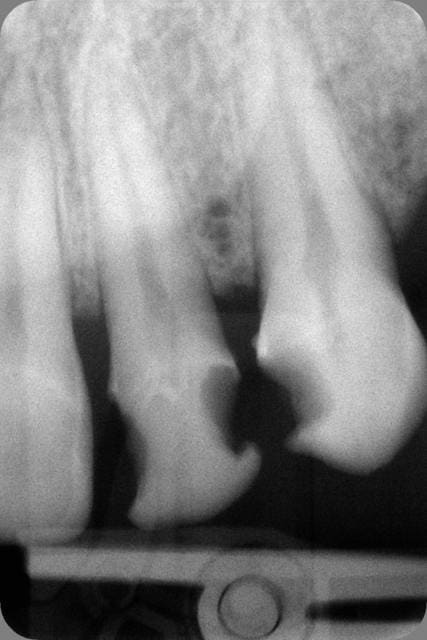

En PJ le dernier specimen, 28 ans, CMU mais dispo que le soir (ben oui il travaille au noir) la bouche en tchernobyl. Je n'ai fait que répondre à sa demande : des dents blanches devant. Pour les extractions allez voir ailleurs.